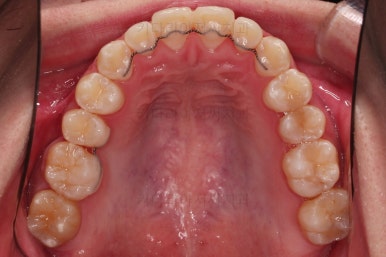

이제 전후 비교를 해볼게요.

1년 7개월 만에 매우 고난이도의 치료를 임플란트 없이 사랑니까지 당겨와서 사용한 만족스러운 치료였습니다.

우측의 결손치아보다 뒤쪽에 있는 치아는 크기나 모양이 원래의 큰 어금니보다 작고 다르게 생겨서 100% 이상적인 교합을 얻기는 한계가 있었어요.

하지만 임플란트 없이 충분히 가능할 수 있게끔 해주어서 환자분도 매우 만족하는 치료가 되었어요.

뿌리도 남아있었고 골 결손도 심했던터라 뒤쪽 치아들이 잘 움직일 것을 고지해 드렸었지만 다행히 거의 문제 없이 치아가 잘 움직였고요.